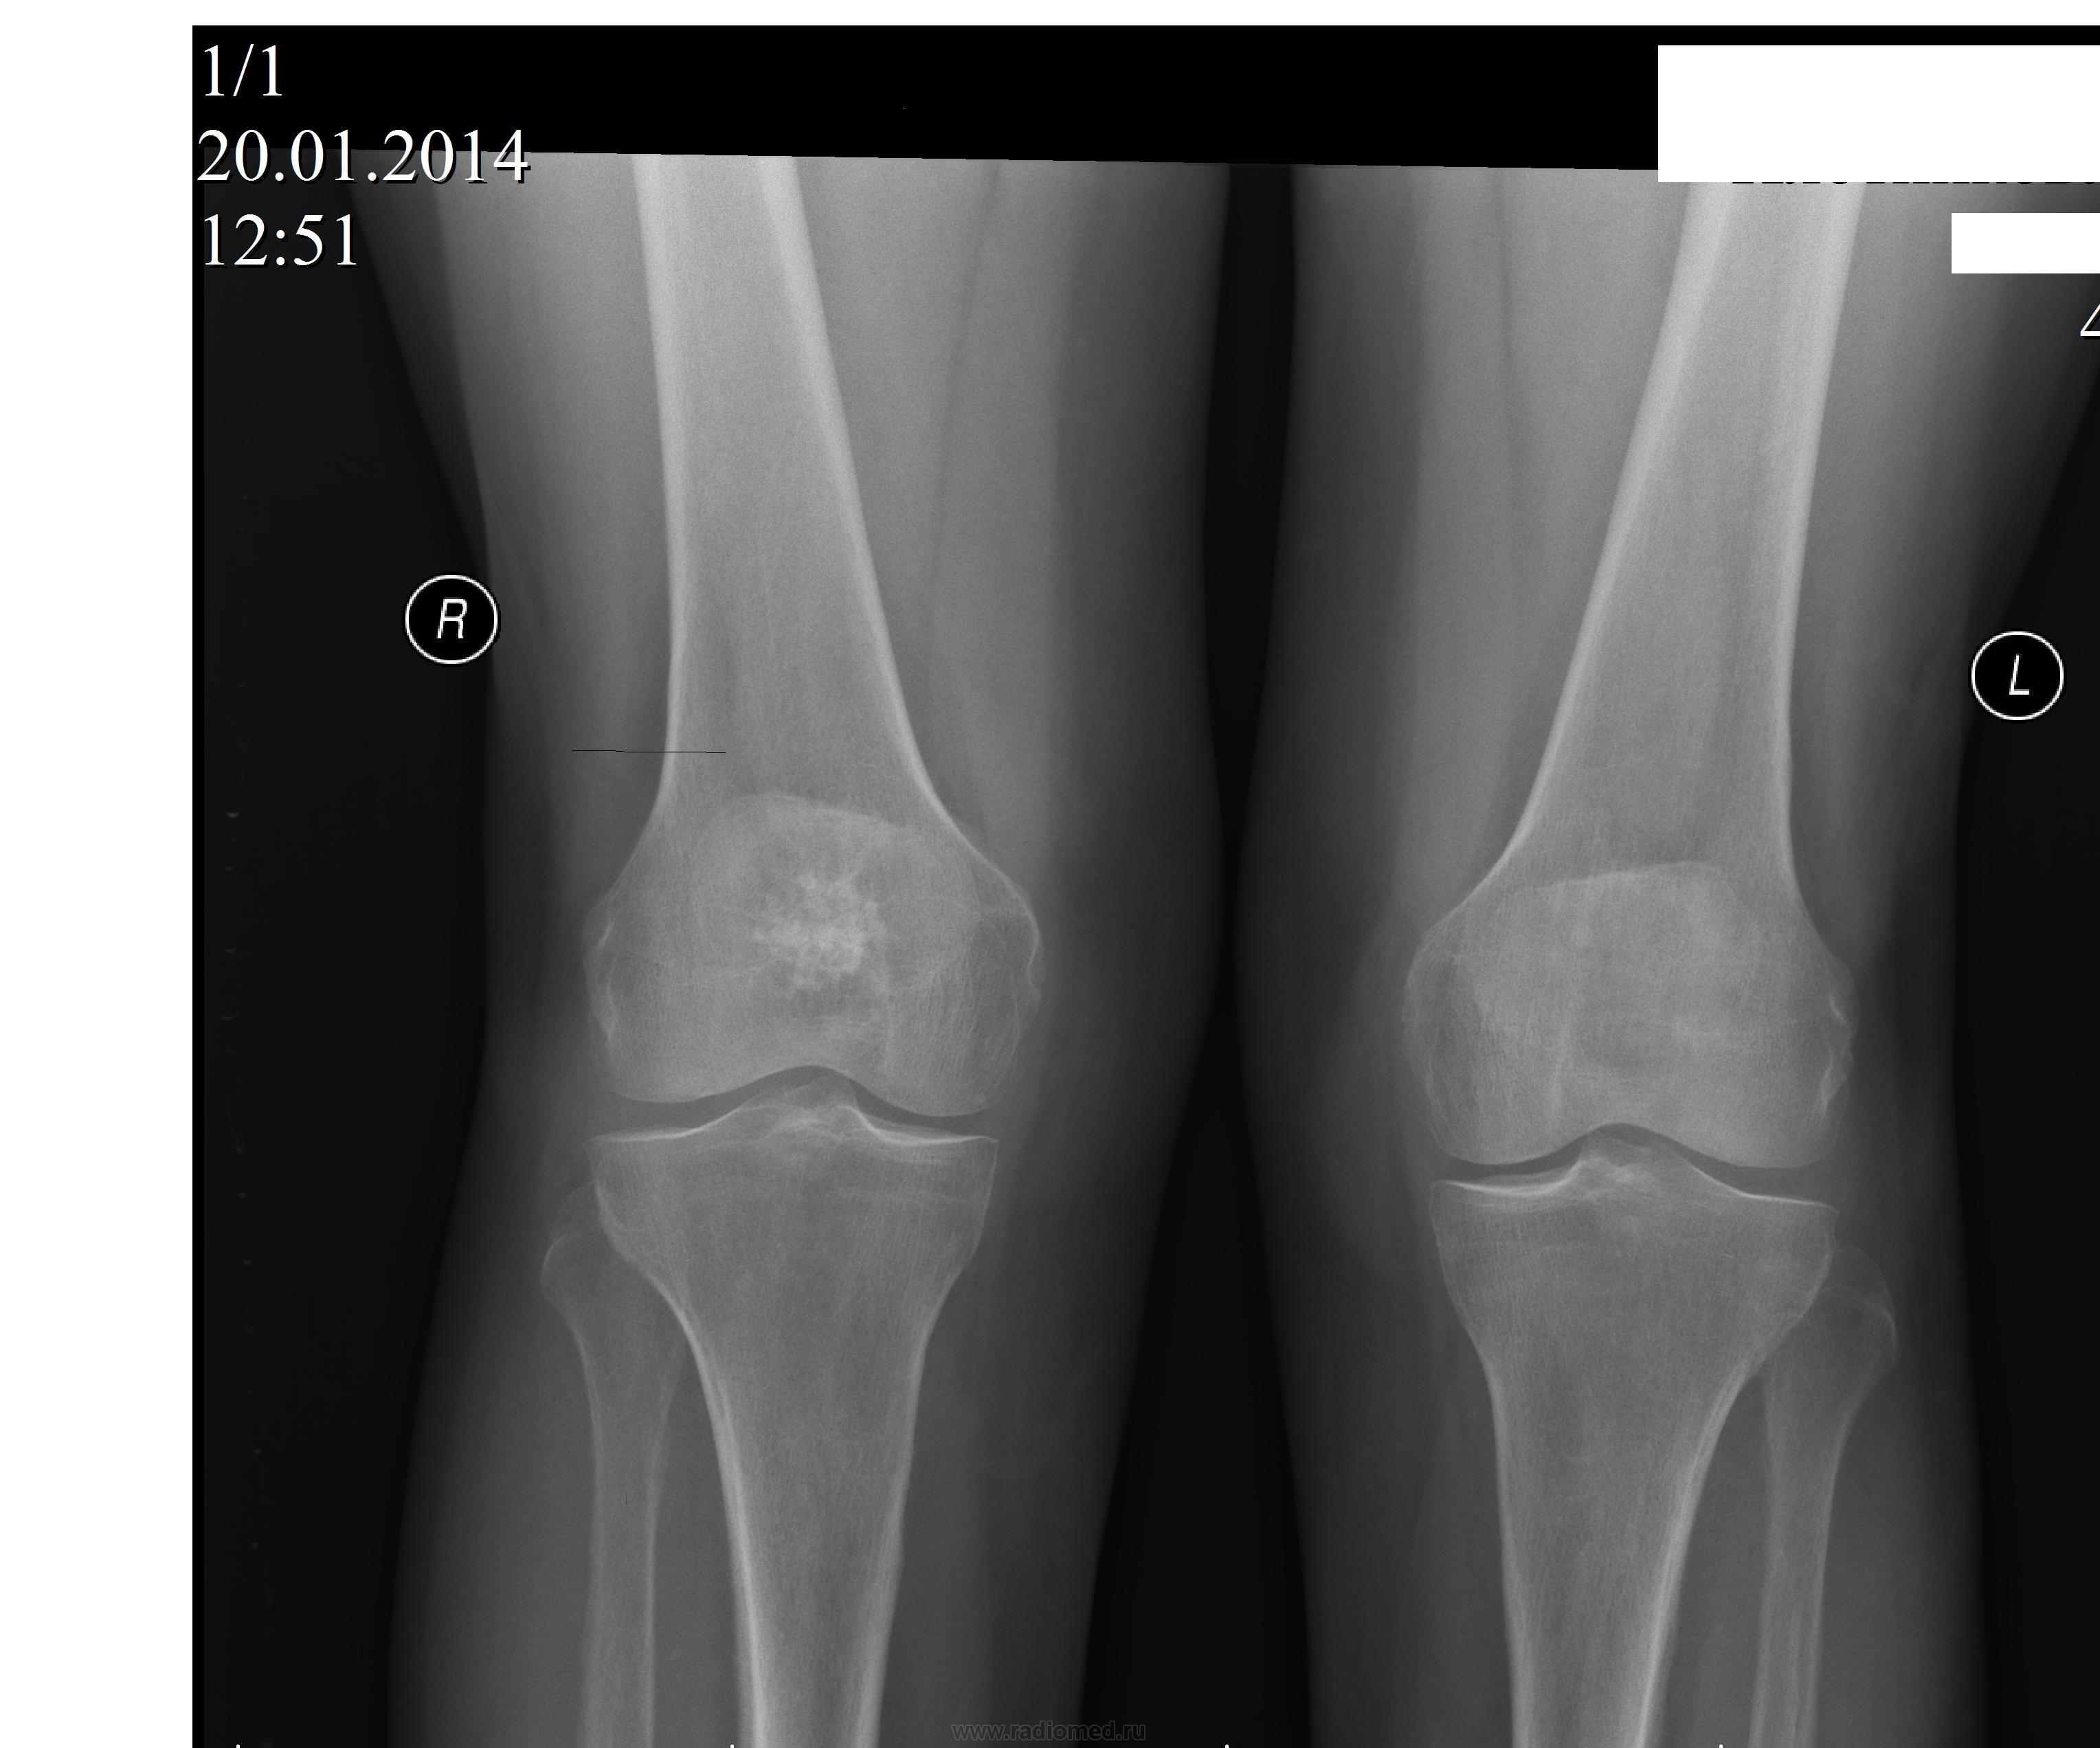

Пол пациента: Женский пол Тип патологии: Доброкачественное новообразование, киста Область исследования: Скелетно-мышечная система Методы исследования: Rg Пациентка 72 года .Жалобы на боли в области коленных суставов.Интересует как надо расценивать, обызвествление в эпиметафизе правой бедренной кости? https://radiomed.ru/sites/default/files/styles/case_slider_image/public/user/406/koleni2.jpg?itok=m3Q9oVz_ https://radiomed.ru/sites/default/files/styles/case_slider_image/public/user/406/koleni4.jpg?itok=k4rvytcG ID:34952 Пнд, 20/01/2014 - 16:46 #1 Almo Не на сайте Был на сайте: 11 часов 59 минут назад Зарегистрирован: 28.09.2008 - 18:50 Публикации: 8304 Больше интересует дальнейшая тактика? Пнд, 20/01/2014 - 17:51 #2 maker4ik Не на сайте Был на сайте: 9 лет 1 день назад Зарегистрирован: 19.10.2011 - 17:49 Публикации: 2682 Инфаркт костного мозга? Пнд, 20/01/2014 - 18:16 #3 Almo Не на сайте Был на сайте: 11 часов 59 минут назад Зарегистрирован: 28.09.2008 - 18:50 Публикации: 8304 Может быть, но как быть уверенным? Пнд, 20/01/2014 - 19:07 #4 Dima Не на сайте Был на сайте: 7 лет 7 месяцев назад Зарегистрирован: 05.08.2012 - 17:39 Публикации: 2467 Мне кажется что все таки больше данных за неопластический процесс, энхондрома как вариант. Терпимость - это когда прощают чужие ошибки; такт - когда не замечают их. (Артур Шницлер) Пнд, 20/01/2014 - 20:23 #5 Андрей Юрьевич Не на сайте Был на сайте: 2 недели 3 дня назад Зарегистрирован: 16.11.2008 - 22:16 Публикации: 18106 Все уже не так просто. Читайте http://www.radiologyassistant.nl/en/p4bc9a97980036/sclerotic-bone-tumors-and-tumor-like-lesions.html , диференцируйте. Андрей Юрьевич Пнд, 20/01/2014 - 22:31 #6 алкс Не на сайте Был на сайте: 10 лет 5 месяцев назад Зарегистрирован: 24.10.2012 - 22:55 Публикации: 2915 Dima wrote: Мне кажется что все таки больше данных за неопластический процесс, энхондрома как вариант. Ну в 72г. скорее инфаркт м.б. чем нео, и вариант Ср, 22/01/2014 - 17:30 #7 ren_gen Не на сайте Был на сайте: 11 лет 6 месяцев назад Зарегистрирован: 30.10.2010 - 19:17 Публикации: 285 энходрома, диф. с вторичной хондросаркомой, менее вероятен инфаркт (картинка не совсем похожа) биопсия поставит точку

Инфаркт костного мозга?

Мне кажется что все таки больше данных за неопластический процесс, энхондрома как вариант.

Ну в 72г. скорее инфаркт м.б. чем нео, и вариант

энходрома, диф. с вторичной хондросаркомой, менее вероятен инфаркт (картинка не совсем похожа)

биопсия поставит точку